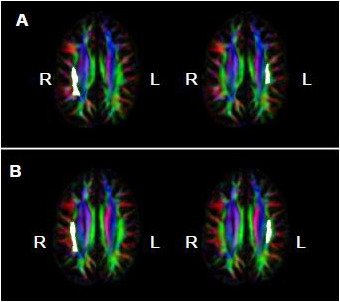

= Amusia. (A) DTT scores and white matter volume of right pars orbitalis (r = 0.507, p = 0.038); (B) DTT scores and gray matter volume of right pars orbitalis (r = 0.479, p = 0.052); (C) DTT scores and FA of right inferior SLF (r = 0.694, p = 0.002); (D) DTT scores and FA of right superior SLF (r = 0.506, p = 0.038).

= Amusia. (A) DTT scores and white matter volume of right pars orbitalis (r = 0.507, p = 0.038); (B) DTT scores and gray matter volume of right pars orbitalis (r = 0.479, p = 0.052); (C) DTT scores and FA of right inferior SLF (r = 0.694, p = 0.002); (D) DTT scores and FA of right superior SLF (r = 0.506, p = 0.038).

= Amusia. (A) DTT scores and white matter volume of right pars orbitalis (r = 0.507, p = 0.038); (B) DTT scores and gray matter volume of right pars orbitalis (r = 0.479, p = 0.052); (C) DTT scores and FA of right inferior SLF (r = 0.694, p = 0.002); (D) DTT scores and FA of right superior SLF (r = 0.506, p = 0.038).

= Amusia. (A) DTT scores and white matter volume of right pars orbitalis (r = 0.507, p = 0.038); (B) DTT scores and gray matter volume of right pars orbitalis (r = 0.479, p = 0.052); (C) DTT scores and FA of right inferior SLF (r = 0.694, p = 0.002); (D) DTT scores and FA of right superior SLF (r = 0.506, p = 0.038).